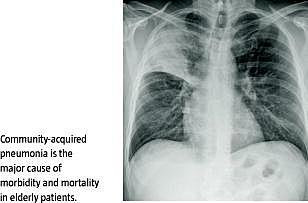

Pneumoni opstået i hjemmet - community acquired pneumonia (CAP) - er en væsentlig årsag til sygelighed og dødelighed hos ældre patienter og den vigtigste dødsårsag i den udviklede verden. Incidensen af indlæggelser af patienter med diagnosen er generelt stigende, og i 2009 blev der indlagt mere end 11.000 personer over 65 år med denne diagnose i Danmark. Optimeret behandling og pleje vil gavne både patienterne og sundhedsøkonomien. Der foreligger evidensbaserede nationale og internationale kliniske retningslinjer for behandling og pleje af patienter med CAP. I et nyligt nationalt kohortestudie fandt man imidlertid regionale forskelle i indlæggelseslængde (LoS), genindlæggelsesfrekvens og mortalitet. Der er således behov for yderligere undersøgelser af forskelle i klinisk praksis for behandling og pleje af denne patientgruppe. Dette studie undersøger læger og sygeplejerskers komplians med kliniske retningslinjer for behandling og pleje af patienter med CAP.